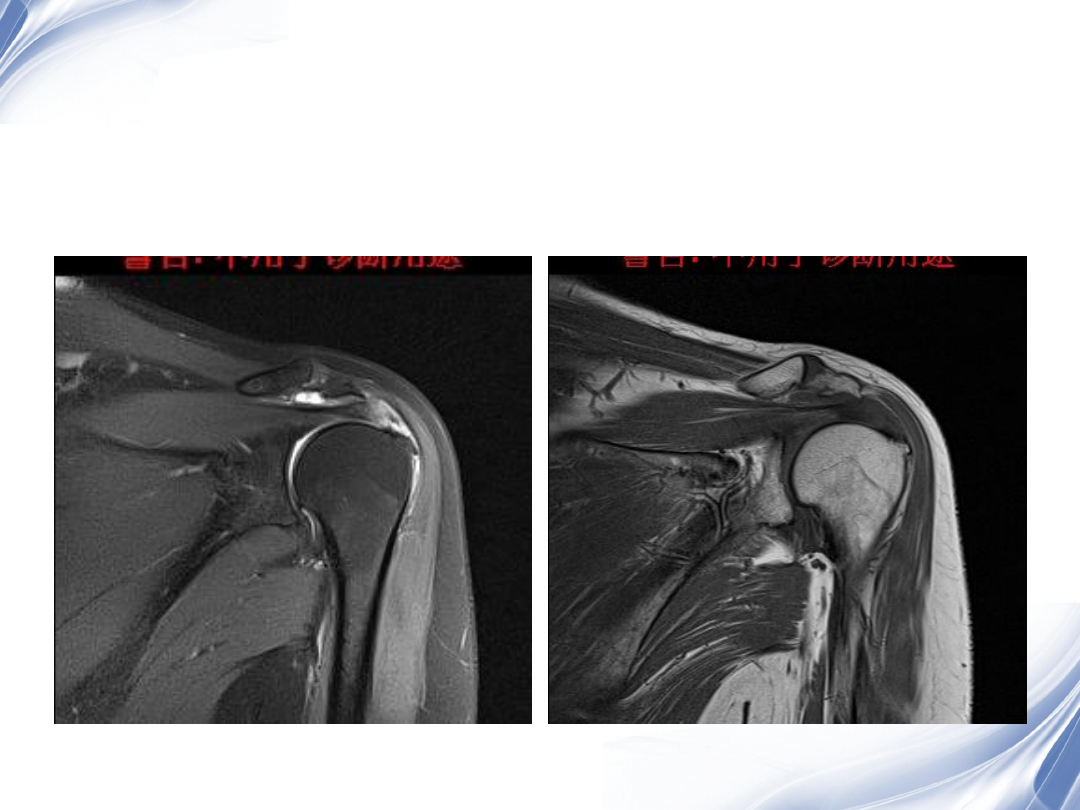

影像学检查

-MRI

最常用

斜冠状面、斜矢状面、横断面

常用的检查序列是

T1WI

T2

压脂

阳性率

95%

24

斜冠状位(临床最常用)

T1

31

34

肩袖全层撕裂

正常MRI